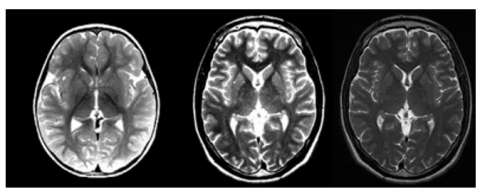

The research dataset originated from Kaggle while containing 3,000 images. Three thousand images in the dataset receive total equal distribution between "Yes" with 1,500 images and "No" also having 1,500 images thereby creating a balanced dataset which can be seen in Figures 8 and 9. A perfectly balanced dataset offers several advantages because it reduces model biases while providing equal representation of the classes which leads to better classification outcomes.

Image resolution and acquisition conditions: The horizontal and vertical resolution of each dataset image equals 96 dots per inch. Image collection takes place through standardized acquisition procedures that create uniformity for minimized brightness and contrast differences as well as noise levels. Standardized acquisition conditions along with these conditions lead to optimized segmentation performance through uniform image quality and format.

Preprocessing requirements: The images receive basic processing steps including dimension standardization through cropping and resizing before they can be employed for educational functions. Pixel intensity values within the dataset benefit from technical preprocessing through intensity normalization as an approach to create consistent values. Model generalization together with pattern detection effectiveness improves with this essential step.

Data distribution that evenly distributes images across the dataset decreases the time needed to manage data especially in situations where classes do not match. An unbalanced dataset causes model predictions to become biased because it enables the model to recognize one class more frequently than the other such as "No Tumor" compared to "Tumor." This dataset maintains a balanced structure which delivers trustworthy and impartial training results to deep learning-based segmentation operations.

Figure 9. Brain MRi images that do not have tumor